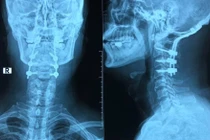

(khoahocdoisong.vn) - BV TƯQĐ 108 tiếp nhận và điều trị cho bệnh nhân N.V.T, 55 tuổi (Hà Nội) nhập viện trong tình trạng chấn thương cột sống cổ, gãy đốt sống C1 do nhảy bể bơi, không để ý mực nước trong bể bơi còn bao nhiêu.